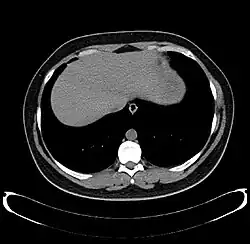

CT scan showing an adult liver in the axial plane

Organogenesis, the development of the organs, takes place from the third to the eighth week during embryonic development. The origins of the liver lie in both the ventral portion of the foregut endoderm (endoderm being one of the three embryonic germ layers) and the constituents of the adjacent septum transversum mesenchyme. In the human embryo, the hepatic diverticulum is the tube of endoderm that extends out from the foregut into the surrounding mesenchyme. The mesenchyme of septum transversum induces this endoderm to proliferate, to branch, and to form the glandular epithelium of the liver. A portion of the hepatic diverticulum (that region closest to the digestive tube) continues to function as the drainage duct of the liver, and a branch from this duct produces the gallbladder.[37] Besides signals from the septum transversum mesenchyme, fibroblast growth factor from the developing heart also contributes to hepatic competence, along with retinoic acid emanating from the lateral plate mesoderm. The hepatic endodermal cells undergo a morphological transition from columnar to pseudostratified resulting in thickening into the early liver bud. Their expansion forms a population of the bipotential hepatoblasts.[38] Hepatic stellate cells are derived from mesenchyme.[39]